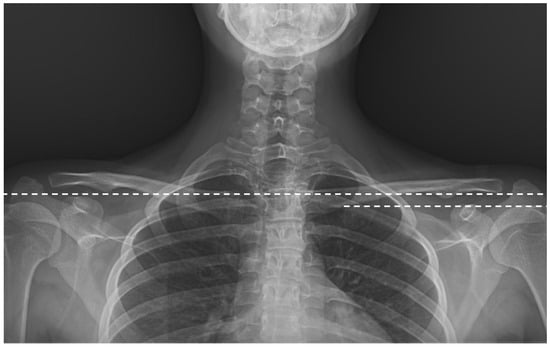

Background/Objective: The anterior vertebral body tethering (AVBT) technique, which preserves spinal mobility and avoids possible fusion problems in adolescent idiopathic scoliosis (AIS) patients, continues to be increasingly used in spine surgery. The study aims to report the early-to-early-mid postoperative radiological results of thoracolumbar/lumbar AVBT on sagittal alignment, and the second aim is to compare AVBT with selective thoracic fusion (STF) and non-selective fusion (NSF) groups in AIS patients. Methods: Patients with a diagnosis of AIS were retrospectively evaluated in the study. All patients were categorized into three groups based on the surgical technique performed: AVBT (n = 17), NSF (n = 19), and STF (n = 15). The major curvature degree, coracoid height difference (CHD), sacral slope (SS), pelvic tilt (PT), pelvic incidence (PI), lumbar lordosis (LL), thoracic kyphosis (TK), cervical lordosis (CL), C7 tilt, sagittal vertical axis (SVA), T1 pelvic angle (TPA), and T1 spinopelvic inclination (T1SPI) were measured for radiological comparison. Scoliosis Research Society-22 (SRS-22) and Oswestry Disability Index (ODI) scores were used at the final follow-up for functional evaluation. Results: The T1SPI value of the NSF group was significantly higher than the STF group in the final follow-up (p = 0.033). The mean decrease of 8.85 ± 7.85 units in the final follow-up value compared to the postoperative CHD value of the patients in the AVBT group was found to be significant (p = 0.028). Statistically significant differences were found between preoperative and the first postoperative CL and TPA measurements (p = 0.001 and p = 0.042, respectively), as well as between preoperative and final follow-up CL measurements in the AVBT group (p = 0.001). No statistically significant differences were observed between the groups in CHD, SS, PT, PI, LL, TK, CL, C7 tilt, SVA, and TPA values (p > 0.05); similarly, the SRS-22 and ODI scores did not differ significantly among the groups (p > 0.05). Conclusions: Thoracolumbar/lumbar AVBT surgery led to significant improvements in shoulder asymmetry and cervical lordosis of AIS patients in the early to early-mid postoperative period. However, compared with spinal fusion techniques, thoracolumbar/lumbar AVBT did not demonstrate superiority in functional scores or sagittal parameters. The mid- to long-term benefits of thoracolumbar/lumbar AVBT remain uncertain and require further investigation. Full article

Figure 1